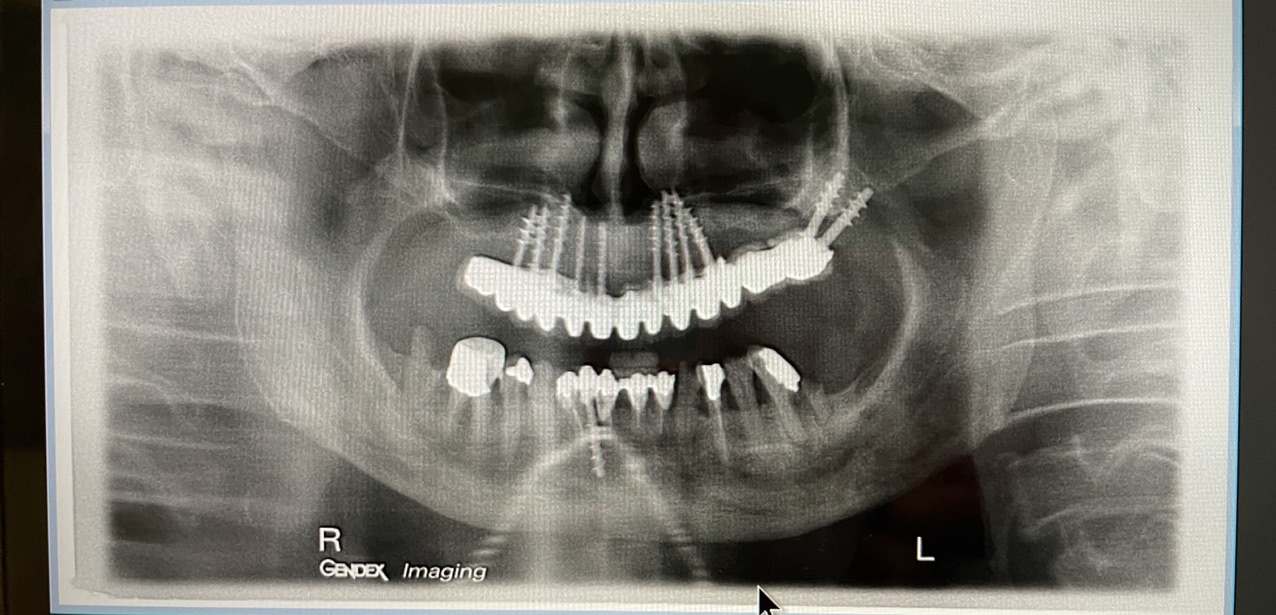

CLINICAL CASE combined with news n.6. Rehabilitation of 04/28/2021

In particular, I consider the following aspects to be significant:

• 5 Presence of implants in the tuber / pterygoid area

• 6 Presence of ancient inclined implants

• 7 Presence of implant bent in 25. (To parallelize it)

• 8 Presence of two mini-plants in 11-12

• 9 Presence of a welded bar in the upper sector

• 10 Severe periodontal disease of the lower sector

• 12 Implant failure of lower Tramonte implant, implant prior to 2004, in the context of general periodontal disease

The images provide additional information in the captions.